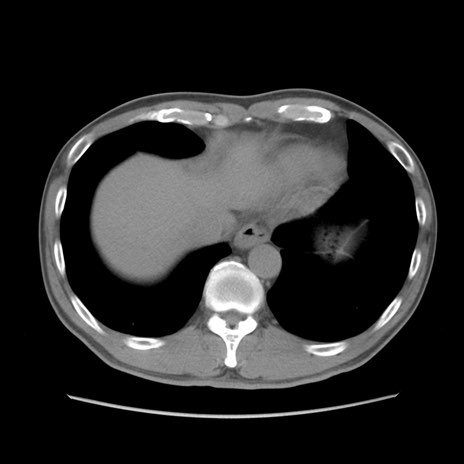

症例56 CT(横断像)

脂肪ウインドウ